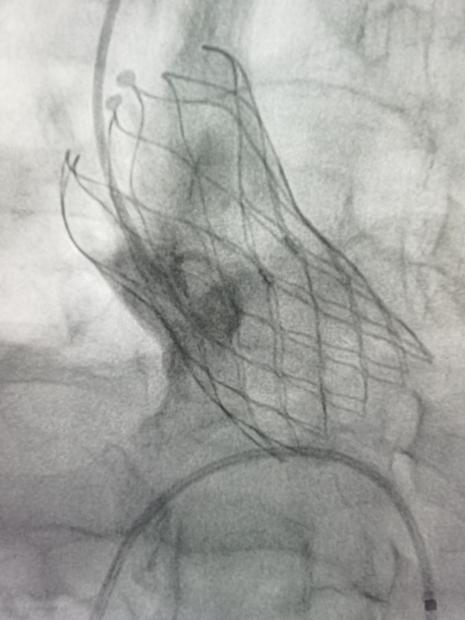

姜永红主任团队对老人病情进行细致分析,因患者高龄,既往有多种慢性病史,无法耐受开胸主动脉瓣置换术,患者主动脉狭窄伴关闭不全,以关闭不全为主,对手术提出了更高的要求。科室及时把老人病情上报医院医务科,院领导高度重视,并多次组织心血管内科、介入科、超声医学科、重症医学科、麻醉手术科、体外循环医师及辅助科室共同讨论,制定手术方案,建议行TAVR手术。于8月3日在心外科医护人员共同努力下,行经股动脉经导管主动脉瓣置换术,手术过程顺利,效果满意。患者术后次日下床活动,精神状态良好。

经导管主动脉瓣置换术(TAVR)是指将组装好的主动脉瓣经导管置入到主动脉根部,替换原有的主动脉瓣,在功能上完成主动脉瓣的置换。TAVR手术是近年来国际上开展的一种新的手术方式,近年来在国内大心脏中心陆续开展,在地市级医院还属于起步阶段。跟外科的开胸手术来对比,TAVR创伤非常小,不需要锯开胸骨及建立体外循环、心脏停跳等危险因素,大大降低了手术风险和术后并发症的发生。对于一些老年人及心功能较差不能耐受开刀手术的心脏瓣膜病人,是一种很好的治疗方式。